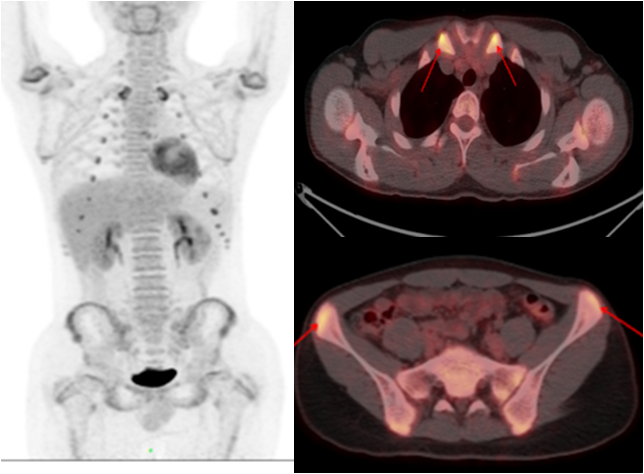

少年男性,間斷發(fā)熱半年,一直未找到原因。PET/CT 顯示多處關節(jié)、軟骨高代謝灶,最終診斷為復發(fā)性多軟骨炎導致的不明原因發(fā)熱,經(jīng)指導后臨床治療效果良好。